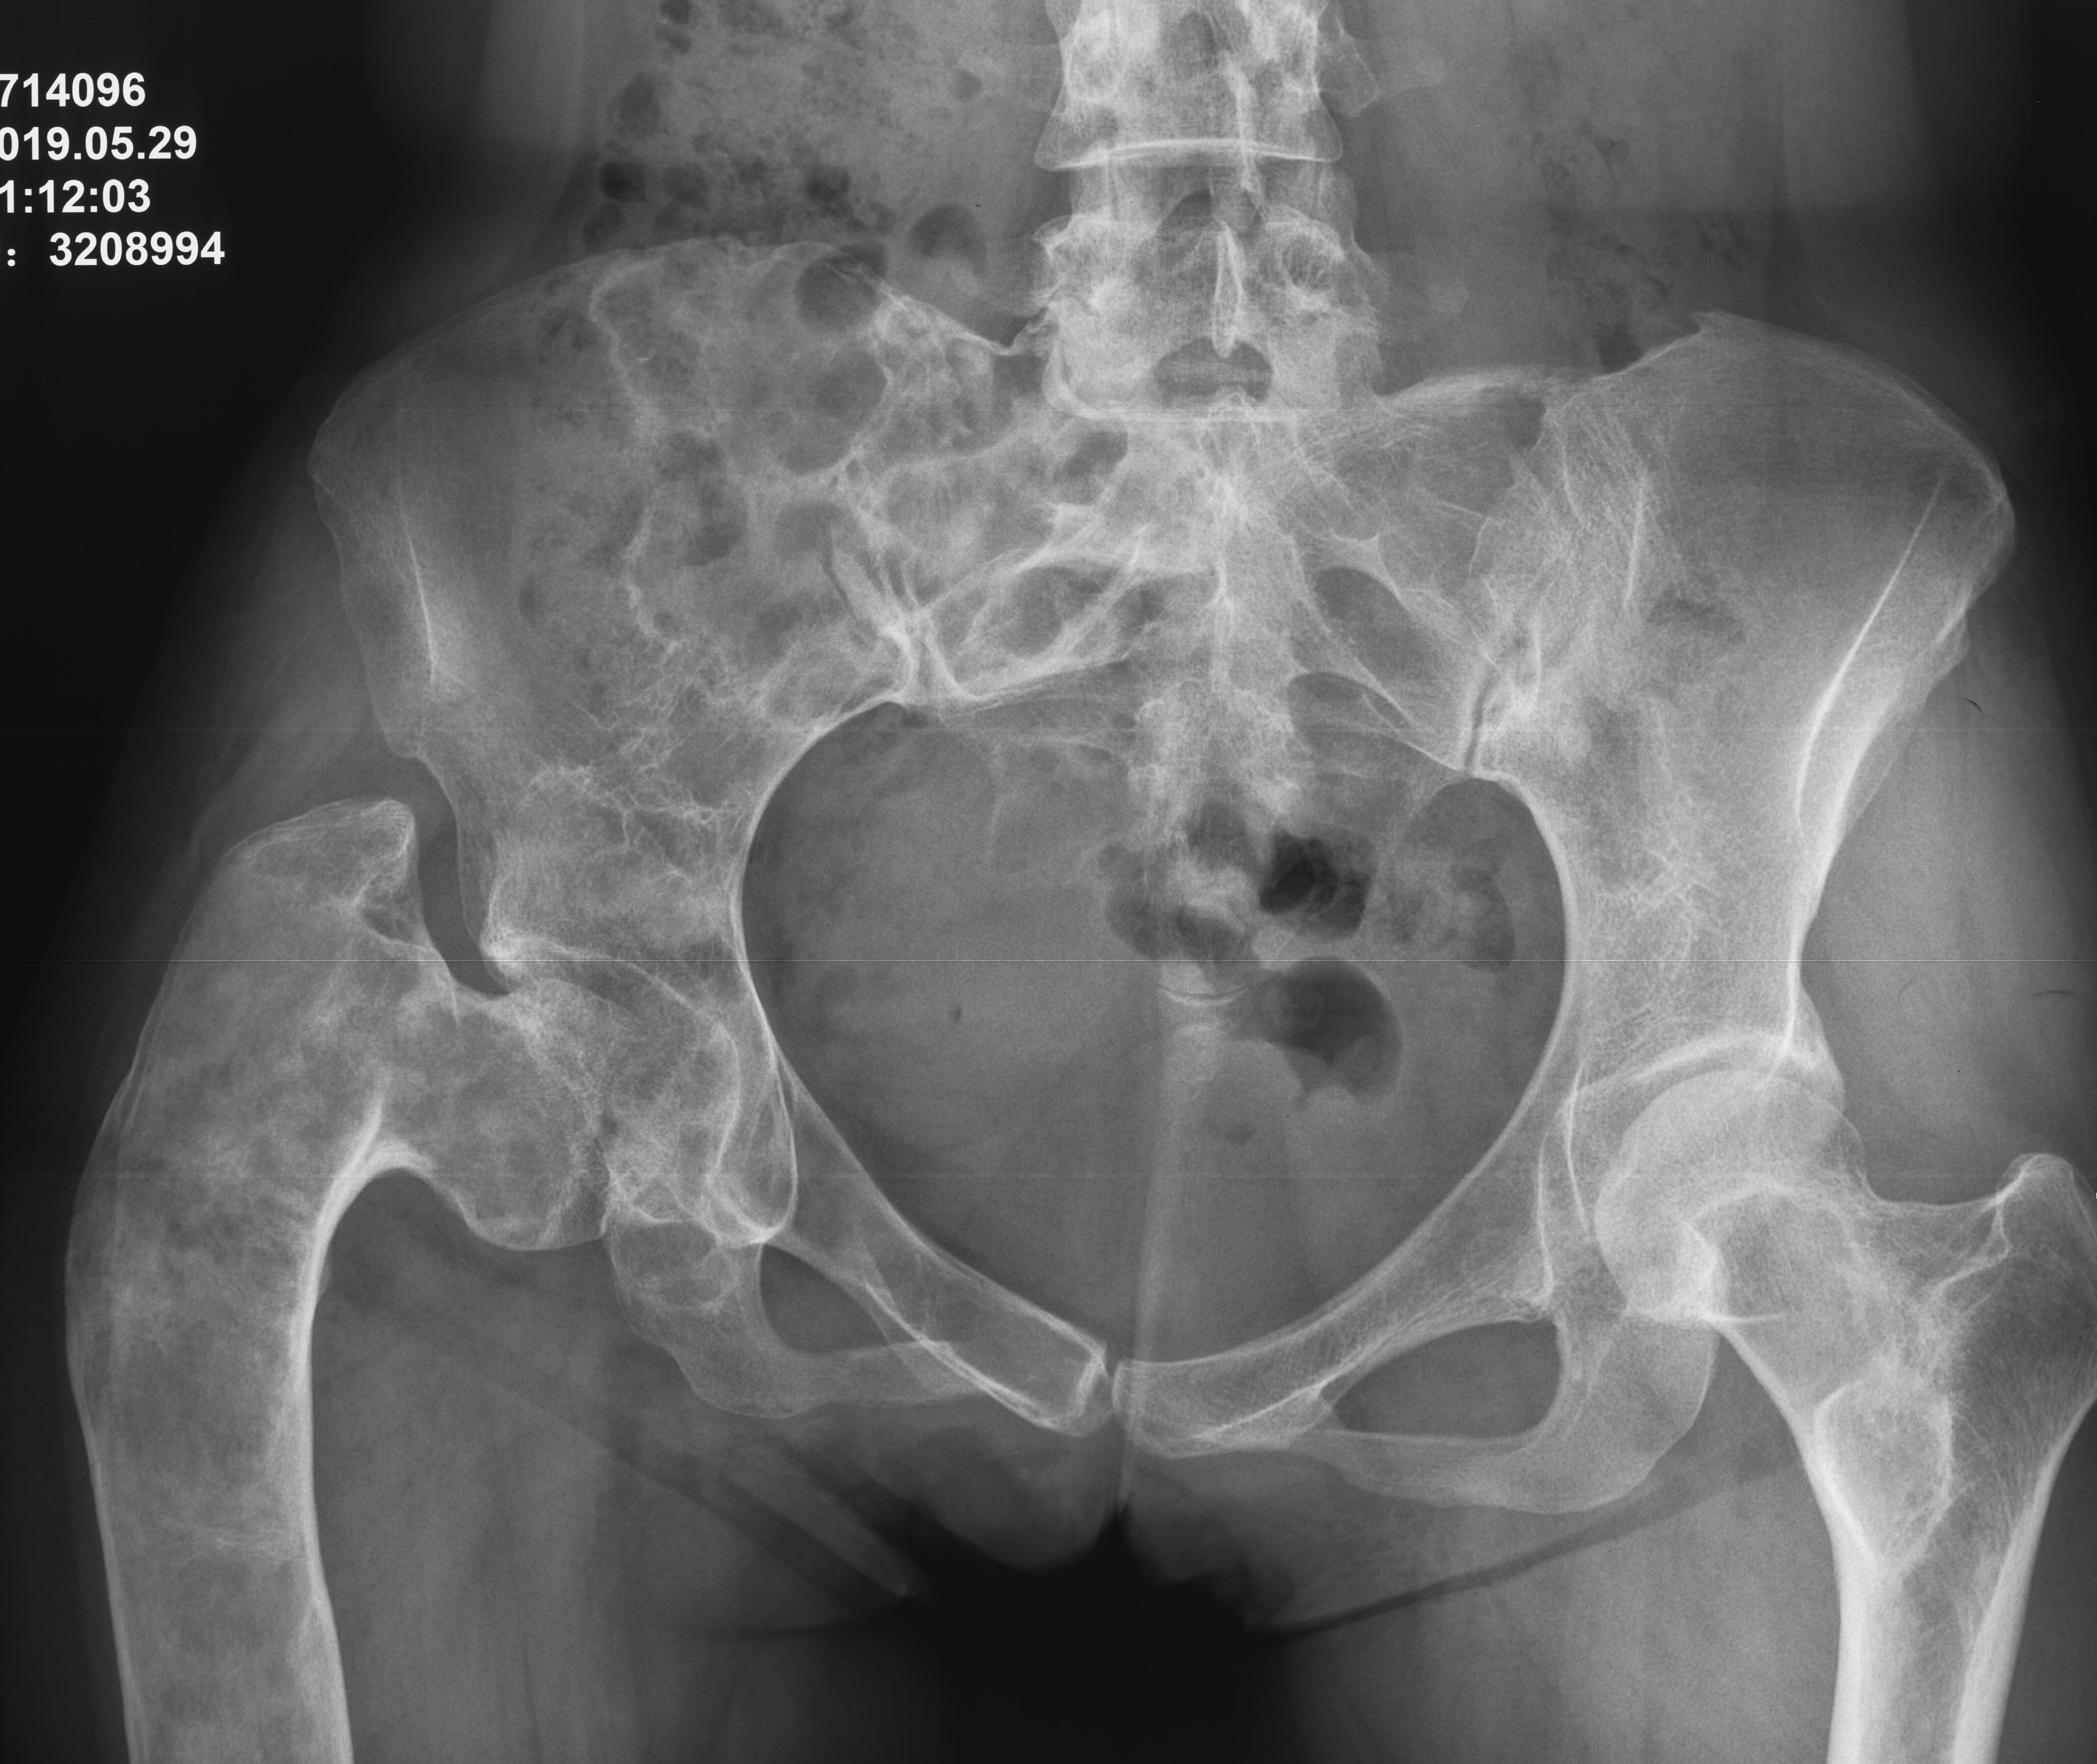

股骨近端骨纖維異樣增殖癥的個體化治療進(jìn)展1、纖維結(jié)構(gòu)不良發(fā)病機(jī)理簡述纖維結(jié)構(gòu)不良(FibrousDysplasia,FD)又稱為骨纖維異樣增殖癥,是一種先天性骨發(fā)育障礙。屬于良性骨樣病損,占所有良性骨腫瘤的7%(JAmAcadOrthopSurg,?2004)。青春期和年輕人多見。由于參與骨代謝的基因(編碼G蛋白亞基)發(fā)生突變,為獲得性功能亢進(jìn)突變,正常體內(nèi)GTP酶活性受到抑制,成骨細(xì)胞內(nèi)cAMP(環(huán)磷酸腺苷)過量產(chǎn)生,正常骨發(fā)育過程障礙,產(chǎn)生了大量異常纖維組織或未成熟的編織骨替代了正常的骨組織(圖1)。此病雖然有基因突變(體細(xì)胞突變),但非遺傳性基因突變(胚胎突變),因此此病不會遺產(chǎn)給下一代。纖維結(jié)構(gòu)不良可為單骨型、多骨型或多骨型合并內(nèi)分泌功能障礙,如合并牛奶咖啡斑和性早熟稱為McCune-Albright綜合征;合并多發(fā)肌內(nèi)粘液瘤,稱為Mazabraud綜合征。圖1:受體G蛋白突變使cAMP(環(huán)磷酸腺苷)過量產(chǎn)生,可刺激垂體、甲狀腺、腎上腺或性腺等;刺激皮膚細(xì)胞產(chǎn)生過量黑色素;出現(xiàn)骨代謝障礙(圖片參考InsightsImaging,2018)。2、纖維結(jié)構(gòu)不良的臨床表現(xiàn)纖維結(jié)構(gòu)不良的臨床表現(xiàn)各種各樣,輕重不一。80%為單骨型,最常見的發(fā)病部位是肋骨、顱骨和股骨;多骨型最常見的部位為顱骨、頜骨、骨盆和股骨。單骨型大多數(shù)患者均為偶然發(fā)現(xiàn),而多骨型在幼年即可被診斷,10歲時出現(xiàn)明顯臨床癥狀,15歲之后不會再出現(xiàn)新的病變部位。單骨型一生中可能不發(fā)展或發(fā)展非常緩慢,但絕不會進(jìn)展為多骨型或Albright綜合征或自行消失。圖2、股骨病變是肢體中最需要外科處理的部位(60%),(圖片參考StrategiesinTraumaandLimbReconstruction,2021)3、纖維結(jié)構(gòu)不良影像學(xué)診斷單骨型和多骨型或合并綜合征的纖維結(jié)構(gòu)不良影像學(xué)表現(xiàn)相同,??蓡螒{X線平片做出診斷。典型的X線表現(xiàn)為膨脹性溶骨性病灶,骨皮質(zhì)變薄,骨皮質(zhì)內(nèi)緣呈扇貝狀,膨脹骨髓腔呈特征性的磨砂玻璃狀。有些小病灶出現(xiàn)較厚的硬化邊。這些征象強烈提示骨纖維結(jié)構(gòu)不良。病變部位沒有正常的骨髓組織和骨基質(zhì),可能出現(xiàn)出血或囊性變,因此纖維結(jié)構(gòu)不良(FD)可繼發(fā)類似于動脈瘤樣骨囊腫(ABC)表現(xiàn)。纖維結(jié)構(gòu)不良病變周圍絕不會出現(xiàn)骨膜反應(yīng)和軟組織腫塊,除非出現(xiàn)了惡性轉(zhuǎn)化,但這種幾率非常罕見。另外,5歲之前一般不建議做骨掃描來除外多骨型,因為在5歲之前的骨掃描不能顯示一些小的病灶,骨掃描正常不能除外多發(fā)性病變。6歲之后所有病變幾乎均可被顯示(InsightsImaging,2018)。沒有癥狀和骨折的患者,2年復(fù)查一次。肢體其他部位的病變不必要每次都進(jìn)行X線片檢查,但對于股骨的病變的患者要求每次復(fù)查X線片,觀察畸形的變化。FD病變可被描述為靜止(穩(wěn)定)、活躍(緩慢生長)和侵襲(生長迅速,并出現(xiàn)疼痛、病理性骨折、神經(jīng)壓迫或惡性轉(zhuǎn)化表現(xiàn))。圖3、靜止性病變。男性40歲(A),女性55歲(B)女性75歲(C)。三名患者均為偶然發(fā)現(xiàn)股骨頸“磨砂玻璃樣”病變,邊緣硬化,無皮質(zhì)破壞,邊界清楚,為典型纖維結(jié)構(gòu)不良表現(xiàn),不需要手術(shù),定期復(fù)查無變化。圖4、活躍或侵襲性病變。女性18歲(A),男性27歲(B),男性14歲(C),女性29歲(D),女性23歲(E),女性30歲,“牧羊拐”(F)。這些都有病理性骨折的風(fēng)險或已存在病理性骨折,需要手術(shù)治療4、為啥需要特別關(guān)注股骨近端纖維結(jié)構(gòu)不良由上可見,無論單骨型還是多骨型,股骨都是臨床上最常見的受累部位。尤其在股骨近端,承受了身體的垂直壓力和旋轉(zhuǎn)應(yīng)力,此部位的骨強度減弱,很容易出現(xiàn)疼痛和病理性骨折,大部分需要外科手段干預(yù)。如下圖,股骨近端出現(xiàn)病理性骨折的比例高達(dá)40%(圖5)。股骨近端病理性骨折或“牧羊拐”畸形矯形在臨床上極具挑戰(zhàn)性!至今沒有確切的關(guān)于股骨近端矯形的臨床指南,報道的病例也是依賴不同大夫的經(jīng)驗,根據(jù)每個患者的具體情況進(jìn)行個體化處理。圖5、股骨近端纖維結(jié)構(gòu)不良(圖片參考JChildOrthop,2014)5、個體化治療股骨近端靜止性病變不建議刮除植骨治療,觀察即可;活躍性病變主要位于股骨頸,股骨粗隆外側(cè)皮質(zhì)正?;颊撸墒褂梦?chuàng)空心釘內(nèi)固定;出現(xiàn)股骨近端病理性骨折的患者,建議DHS動力髖螺釘、股骨近端鋼板或近段髓內(nèi)針治療,如果同時存在股骨弓狀畸形,可同時截骨矯正股骨畸形或待骨折愈合后二期再處理;對于股骨近端“牧羊拐”截骨矯形后使用股骨全長髓內(nèi)針恢復(fù)下肢力線是相對比較公認(rèn)的內(nèi)固定手段。纖維結(jié)構(gòu)不良的治療既往認(rèn)為需要處理病灶、植骨,但現(xiàn)在認(rèn)為應(yīng)該以預(yù)防和避免病理性骨折,或畸形矯正為主要目的。遵循矯形原則,恢復(fù)下肢力線和活動功能,F(xiàn)D截骨矯形后骨愈合能力沒有問題(JBoneJointSurgAm,?1998;JChildOrthop,2014;OrphanetJournalofRareDiseases,2018;StrategiesinTraumaandLimbReconstruction,2021)。6、兒童患者的治療難點兒童患者的特點是股骨頭骨骺和大粗隆骨骺沒有閉合,且股骨髓腔較細(xì),股骨近端直徑小,常規(guī)成人髓內(nèi)針和DHS動力髖螺釘、股骨近端解剖板可能損傷骨骺或無法使用。矯形后隨著年齡增長,畸形容易復(fù)發(fā),且某些多骨型患者股骨近端、股骨頸和股骨頭可能都受累,內(nèi)固定不牢固,容易失敗。出現(xiàn)股骨近端病理性骨折的患者,可以使用成人肱骨髓內(nèi)針或肱骨近端解剖鋼板替代,但需要與家屬充分溝通,手術(shù)只是穩(wěn)定骨折,對疾病發(fā)展沒有實質(zhì)性作用。對于無癥狀無病理性骨折兒童患者是否需要過于積極的進(jìn)行早期處理和畸形矯正沒有定論。7、藥物治療進(jìn)展纖維結(jié)構(gòu)不良的溶骨性破壞有破骨細(xì)胞參與,RANKL通路活躍,臨床上既往應(yīng)用二膦酸鹽制劑,如唑來膦酸等輔助治療纖維結(jié)構(gòu)不良,近來逐漸被地舒單抗替代,原因在于地舒單抗臨床使用方便,且在回顧性多中心研究中顯示對于唑來膦酸無效的患者,使用地舒單抗仍然有效(Bone,2023)。雖然目前地舒單抗在臨床上應(yīng)用于纖維結(jié)構(gòu)不良為超適應(yīng)證用藥,但在纖維結(jié)構(gòu)不良患者上應(yīng)用是安全有效的(NEnglJMed,2023)。對于纖維結(jié)構(gòu)不良患者使用地舒單抗,需要應(yīng)用前告知患者。8、典型病例1)女性,30歲,右股骨近端病理性骨折,微創(chuàng)空心釘內(nèi)固定,人工骨注射。術(shù)后1個月活動錄像2)男性31歲,因疼痛發(fā)現(xiàn)左股骨近端纖維異樣增殖癥,病理性骨折。手術(shù)采用病灶刮除,自體腓骨和異體骨植入,鋼板內(nèi)固定術(shù)。術(shù)后2.5年復(fù)查,骨折愈合良好,無復(fù)發(fā),患者日?;顒雍瓦\動完全正常(錄像)3)、男性,28歲,疼痛發(fā)現(xiàn)右股骨近端纖維異樣增殖癥,骨折風(fēng)險很高,建議手術(shù),然而在等待住院期間行走時突然摔倒,出現(xiàn)病理性骨折,急診手術(shù)4)、男性,43歲,年輕時在當(dāng)?shù)匦杏夜晒腔纬C正鋼板內(nèi)固定,但矯正不滿意?,F(xiàn)股骨近端出現(xiàn)病理性骨折。這個病人首先處理病理性骨折,將原固定鋼板取出,股骨近段髓內(nèi)針骨折內(nèi)固定,待二期再進(jìn)行股骨畸形矯正5)、男性,29歲,左股骨近端“牧羊拐”畸形,兒時曾行股骨彈性針置入,隨著年齡增長,畸形仍持續(xù)加重,現(xiàn)雙下肢相差7cm,患者行走跛行重,患者體重也較大,活動后容易疲勞不適,影響正常生活。制定詳細(xì)手術(shù)計劃,我們使用最新的3D打印技術(shù),術(shù)前計算機(jī)模擬截骨角度,髓內(nèi)針植入長度和位置,矯形后效果等。術(shù)中通過3D截骨導(dǎo)板,精確截骨矯形,髓內(nèi)針內(nèi)固定。患者矯形后雙下肢基本等長,隨訪骨折愈合良好。術(shù)后三個月復(fù)查,建議逐漸脫拐(活動錄像)9、總結(jié)股骨近端纖維結(jié)構(gòu)不良容易出現(xiàn)病理性骨折或合并“牧羊拐”畸形,其臨床治療充滿挑戰(zhàn),包括手術(shù)內(nèi)固定的選擇、骨質(zhì)條件差、是否一期進(jìn)行矯形、矯形可能需要進(jìn)行多次手術(shù)以及兒童股骨近端纖維結(jié)構(gòu)不良的治療等。目前沒有現(xiàn)成的指南應(yīng)用,強調(diào)個體化治療。隨著3D打印技術(shù)的出現(xiàn),術(shù)前制定詳細(xì)的手術(shù)計劃,術(shù)中精確截骨矯形是最大進(jìn)展,為手術(shù)帶來了便利,患者也獲得了良好的手術(shù)收益-風(fēng)險比。